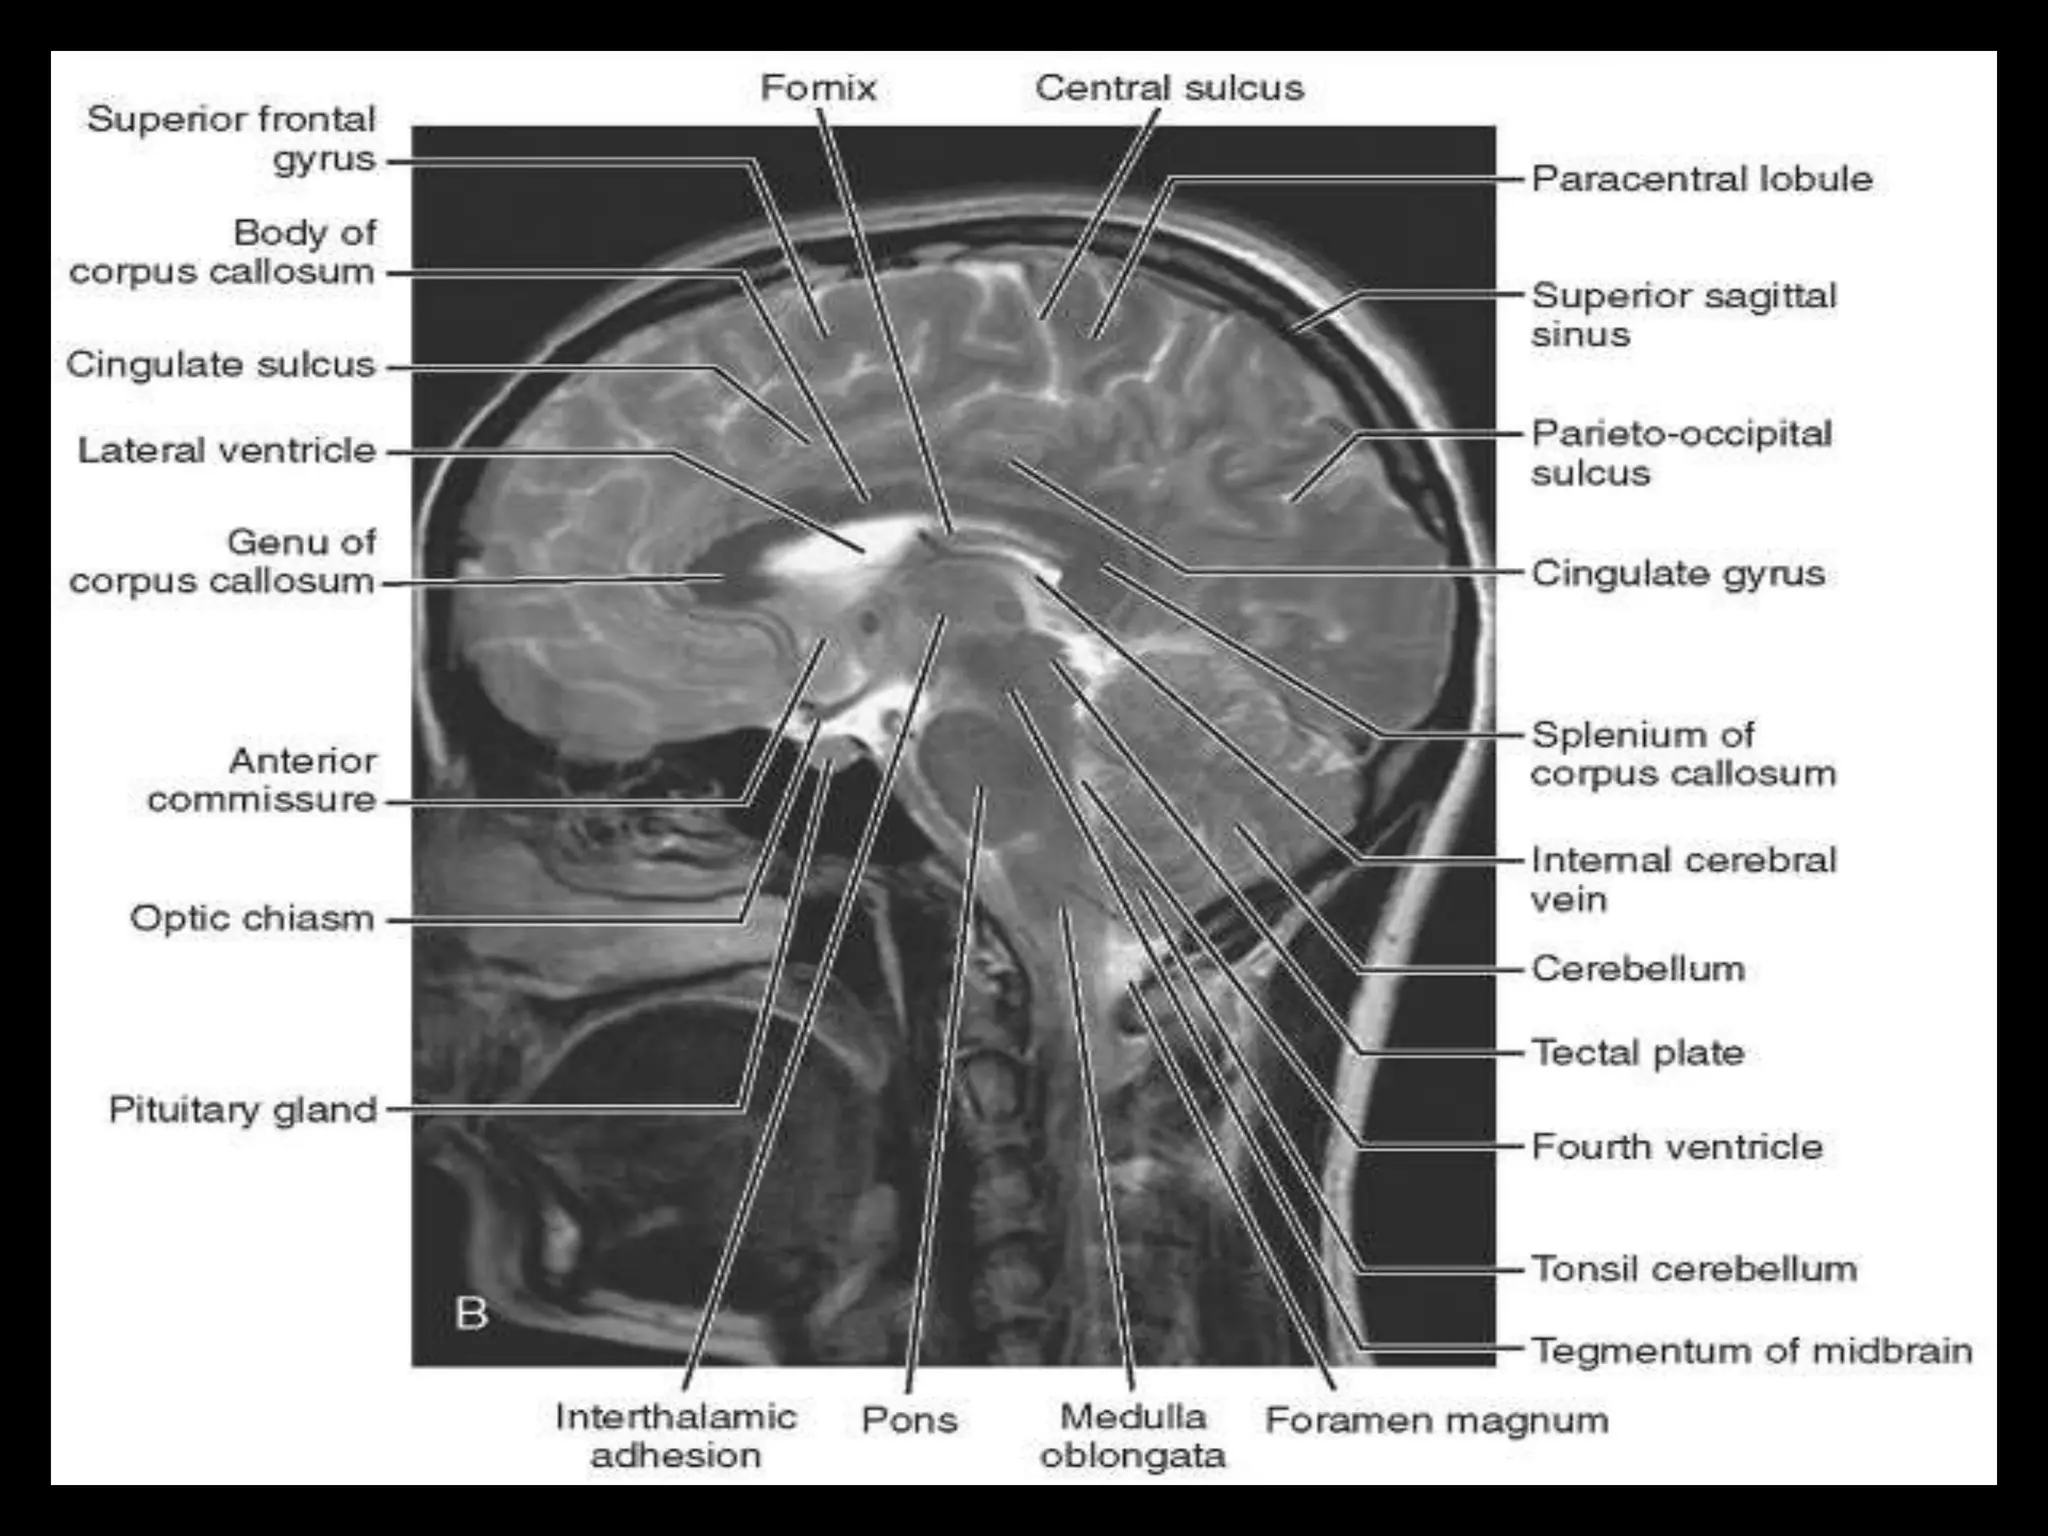

On CT and MR scans, the brain has been briefly viewed in

infratentorial and supratentorial sections, as described below.

CT scans are performed with a 15- to 20-degree angulation to

the canthomeatal line at 8-mm increments. MRI scans are

generally obtained parallel to the AC-PC line in the axial plane

with 6-mm slice thickness. Using the sagittal view, the coronal

sections are acquired parallel to the brain stem, and the

sagittal sections are obtained perpendicular to the axial

section.

Sectional Anatomy: NormalAxial CT and MRI Anatomy. On CT and MR scans, the brain has been briefly viewed in infratentorial and supratentorial sections, as described below. CT scans are performed with a 15- to 20-degree angulation to the canthomeatal line at 8-mm increments. MRI scans are generally obtained parallel to the AC-PC line in the axial plane with 6-mm slice thickness. Using the sagittal view, the coronal sections are acquired parallel to the brain stem, and the sagittal sections are obtained perpendicular to the axial section. On MRI studies, cranial nerves IX and X can be demonstrated at this level because they emerge from the postolivary sulcus. The posterior aspect of the cerebellar hemispheres is outlined by the inferior portion of the cisterna magna.